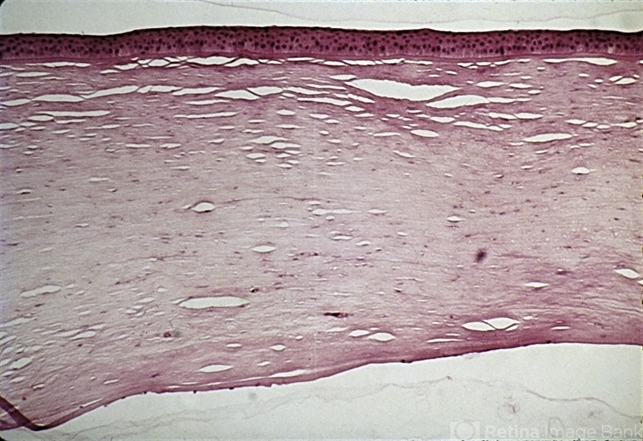

- interstitial keratitis, stroma

- In interstitial keratitis, the only pathology noted is the presence of blood vessels in the deep stroma.